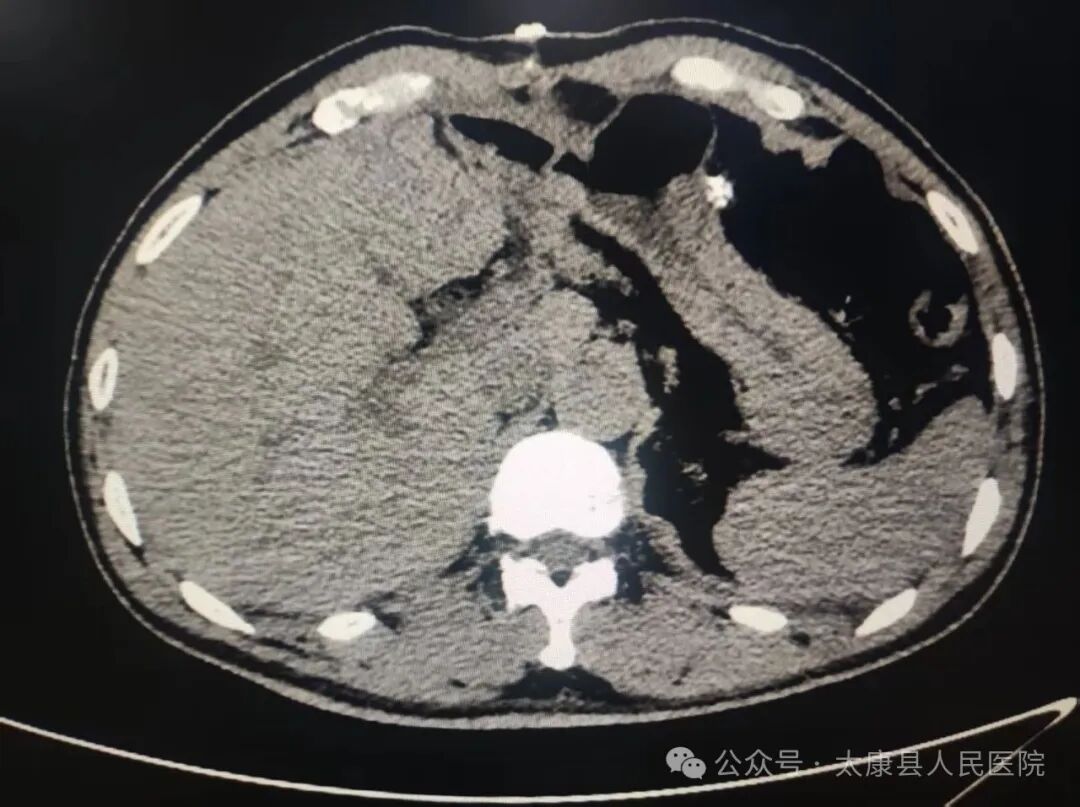

患者因"间断腹痛1天余"入院,经CT及MRCP检查诊断为:肝内胆管多发结石并胆管扩张、阑尾炎若采用传统开腹手术,需25cm以上切口,创伤大、恢复慢。

手术过程中,刘进学主任凭借丰富的临床经验和娴熟的操作技巧,联合麻醉科副主任医师王晓东、手术室护士长张翠华等医护人员精准完成“腹腔镜下肝左外叶切除+胆管切开取石T管引流术+胆道镜探查+胆囊切除术+阑尾切除术”等多个手术步骤。术后复查显示肝内结石清除干净,患者恢复良好。